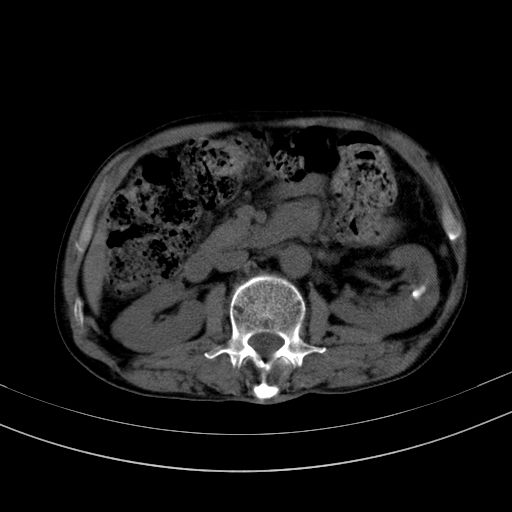

以下是引用37度在2010-1-9 14:37:00的发言:[br]1.双肾囊肿,左肾积水结石,.胆总管轻度扩张;[br]2.病灶在腹膜外,考虑纤维瘤。

以下是引用dyqct在2010-1-9 17:56:00的发言:[br]考虑:1.双肾囊肿,左肾积水结石、旋转不良。[br] 2.右侧腹直肌血肿或纤维瘤。[br]肠道准备不好。做个增强。